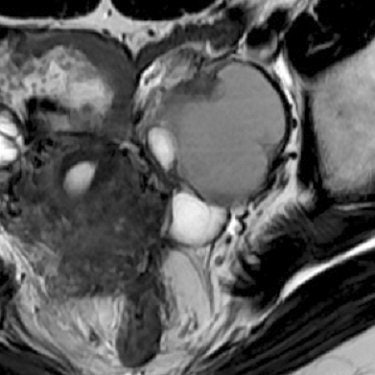

The shading sign, caused by the T2 shortening in an adnexal cyst, is an MR feature of endometriosis and is helpful for making the differential diagnosis, Takeuchi explained. In addition, the hemosiderin-laden macrophage deposits in the cyst wall are another pathologic feature of endometrial cysts, which results in signal voids on SWI.

"Because susceptibility-induced signal intensity loss may increase from 1.5T to 3T, the shading sign on T2-weighted images and signal voids due to hemosiderin deposition on SWI may (be) well visualized on 3T," Takeuchi and colleagues wrote in their ISMRM abstract.

According to the results, signal intensity of the cysts was lower at 3-tesla MRI than at 1.5-tesla based on visual inspection. The cyst-to-muscle SIR on 3-tesla imaging was 2.04 ± 0.90 versus 4.72 ± 2.34 on 1.5-tesla MR. The shading sign was seen on 3-tesla MR, but not on 1.5-tesla MR, in two lesions.

| Endometrial cyst with the shading sign on T2-weighted 3-tesla MRI (above), which was not demonstrated on T2-weighted 1.5-tesla MR (below). Images courtesy of Dr. Mayumi Takeuchi. |